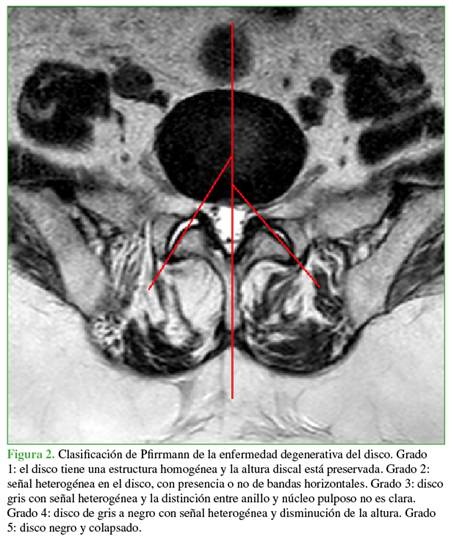

Se evaluaron las imágenes de resonancia magnética (se utilizó un resonador de alto campo Siemens Espree 1.5 Tesla) de 300 niveles L4-L5 y L5-S1 (de 87 mujeres y 63 hombres, con un rango etario de 33 a 82 años), midiendo los grados de inclinación facetaria bilateralmente (Figura 1), la diferencia entre la inclinación de las facetas de ambos lados y el grado de degeneración discal de acuerdo con la clasificación de Pfirrmann9 (Figura 2).

Para esto último se dividió a los pacientes en dos grupos: con EDD leve (grados 1, 2 y 3 de la clasificación de Pfirrmann) o severa (grados 4 y 5). Se consideró que había TF ante una diferencia de 5° entre la inclinación facetaria de un lado y otro.1,10 Los ángulos facetarios se midieron en el corte axial medio del disco en cuestión, paralelo al platillo inferior de la vértebra superior.